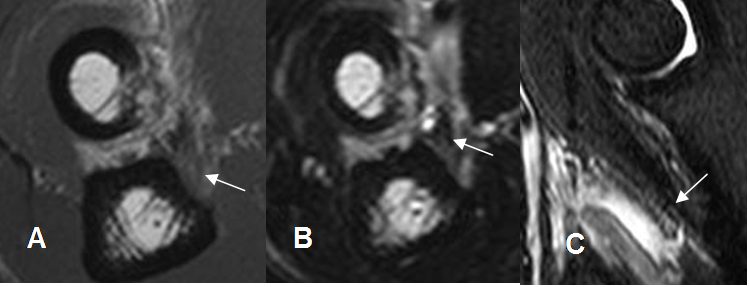

El método de elección para la exploración de esta patología, es la RM, sobre todo en los

casos de ruptura parcial o en ausencia de retracción. (16).

El trauma del tendón distal del bíceps, es mejor evaluado con secuencias sagitales en T2 o STIR. (3).

En la ruptura parcial, se aprecia el tendón adelgazado. En la completa ausencia, con

presencia de líquido sobre la inserción y retracción en grado variable. (3). (Fig 39, 40 A y 40 B).

Fig 39. Ruptura parcial en tendón del biceps.

A: RM axial en T1 y B: RM axial en T2. Hiperintensidad sobre la inserción del biceps, por ruptura parcial.

C: RM sagital en STIR. Hiperintensidad en la inserción del bíceps, con cambios inflamatorios asociados.